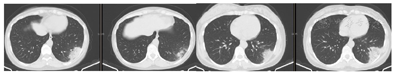

此时,与其共同居住的例2(儿媳)和例3(孙女)也出现发热,体温最高38.6℃,例2还伴有明显头痛,血象不高,流感检测阴性,胸部CT也显示左肺下叶外后基底段胸膜下片状实变影(图2)。

当诊断陷入困境,一筹莫展之时,患者共同居住的儿媳和孙女同时发热,为诊断带来转机。"有趣"的是,例2(儿媳)的症状与例1(患者)的病情很是相似,都表现为发热和明显的神经系统症状,化验血象不高,连胸部CT也表现为同样的部位和形态。这也引发了我们极大的关注。千头万绪,还是要从患者身上找答案。出于感染科医生的职业敏感性,通过详细的流行病学询问,获悉患者家中饲养两只鹦鹉半年,近一月内相继死亡,因此联想到和鹦鹉相关的人畜共患病——鹦鹉热,并在第一时间给婆媳二人选择了合适的药物治疗,为改善预后赢得了时间。更为难得而且重要的是,后续的支气管肺泡灌洗液mNGS检测结果也印证了我们的临床判断,原来鹦鹉才是此次家庭聚集性肺炎发病的元凶。

鹦鹉热的实验室检查缺乏特异性,血常规白细胞通常正常,但分类可有核左移。C反应蛋白、血沉通常明显升高。肝酶轻度升高和低钠血症常见。微量免疫荧光法检测血清鹦鹉热衣原体抗体是常用的诊断手段,血清抗体滴度四倍以上变化,或抗体滴度>16,具有诊断意义,但我国各医院的实验室并不常规开展该检测。鹦鹉热衣原体的培养技术难度高,并且培养时有高度传染性,只能在生物安全级别3级以上的特殊实验室进行。传统病原学诊断技术存在诸多缺陷,基于宏基因组测序的病原检测技术显示出了巨大的应用价值,近年来国内外关于鹦鹉热文献报道几乎都来自于mNGS测序结果[3]。鹦鹉热胸部影像学可以表现为不同程度的实变和渗出,多表现为胸膜下实变影,下肺多见。实变累及范围与病情严重程度相关。胸腔积液少见[1,3,10,11,12]。